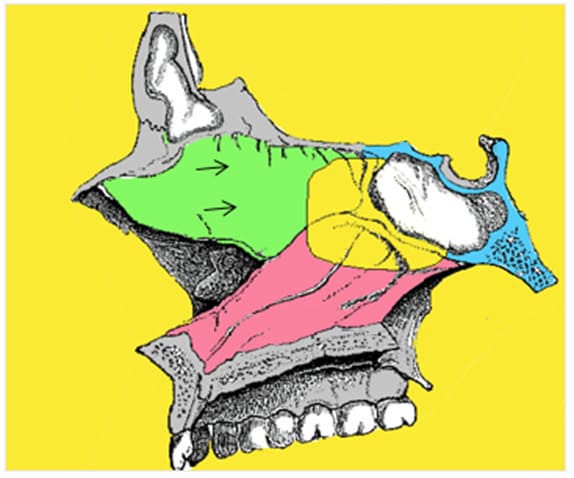

Another important space is the lateral recess. It is found in well-developed sphenoid sinuses, where it is formed by pneumatization of the superior portion of the pterygoid process. Two important structures limit the lateral recess medially: the Vidian nerve lying in the Vidian canal inferiorly and the maxillary nerve (V2) superiorly, at the level of the foramen rotundum. These structures can be identified on a CT-scan. A lateral recess is correlated with a greater distance between those two nerves. Thus, it informs on the potential risk to neurovascular structures. This is important when using the transnasal approach for middle cranial fossa surgery (12).